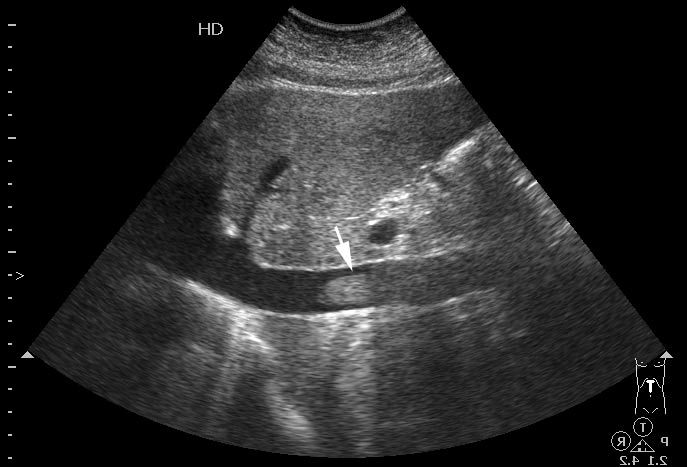

УЗИ: тромб в НПВ

Женщина средних лет из терапевтического отделения, диагноз - острая внегоспитальная пневмония.

tags: IVC thrombosis, sonography

Это тромб в НПВ. А что в клинике? Интересно ЦДК